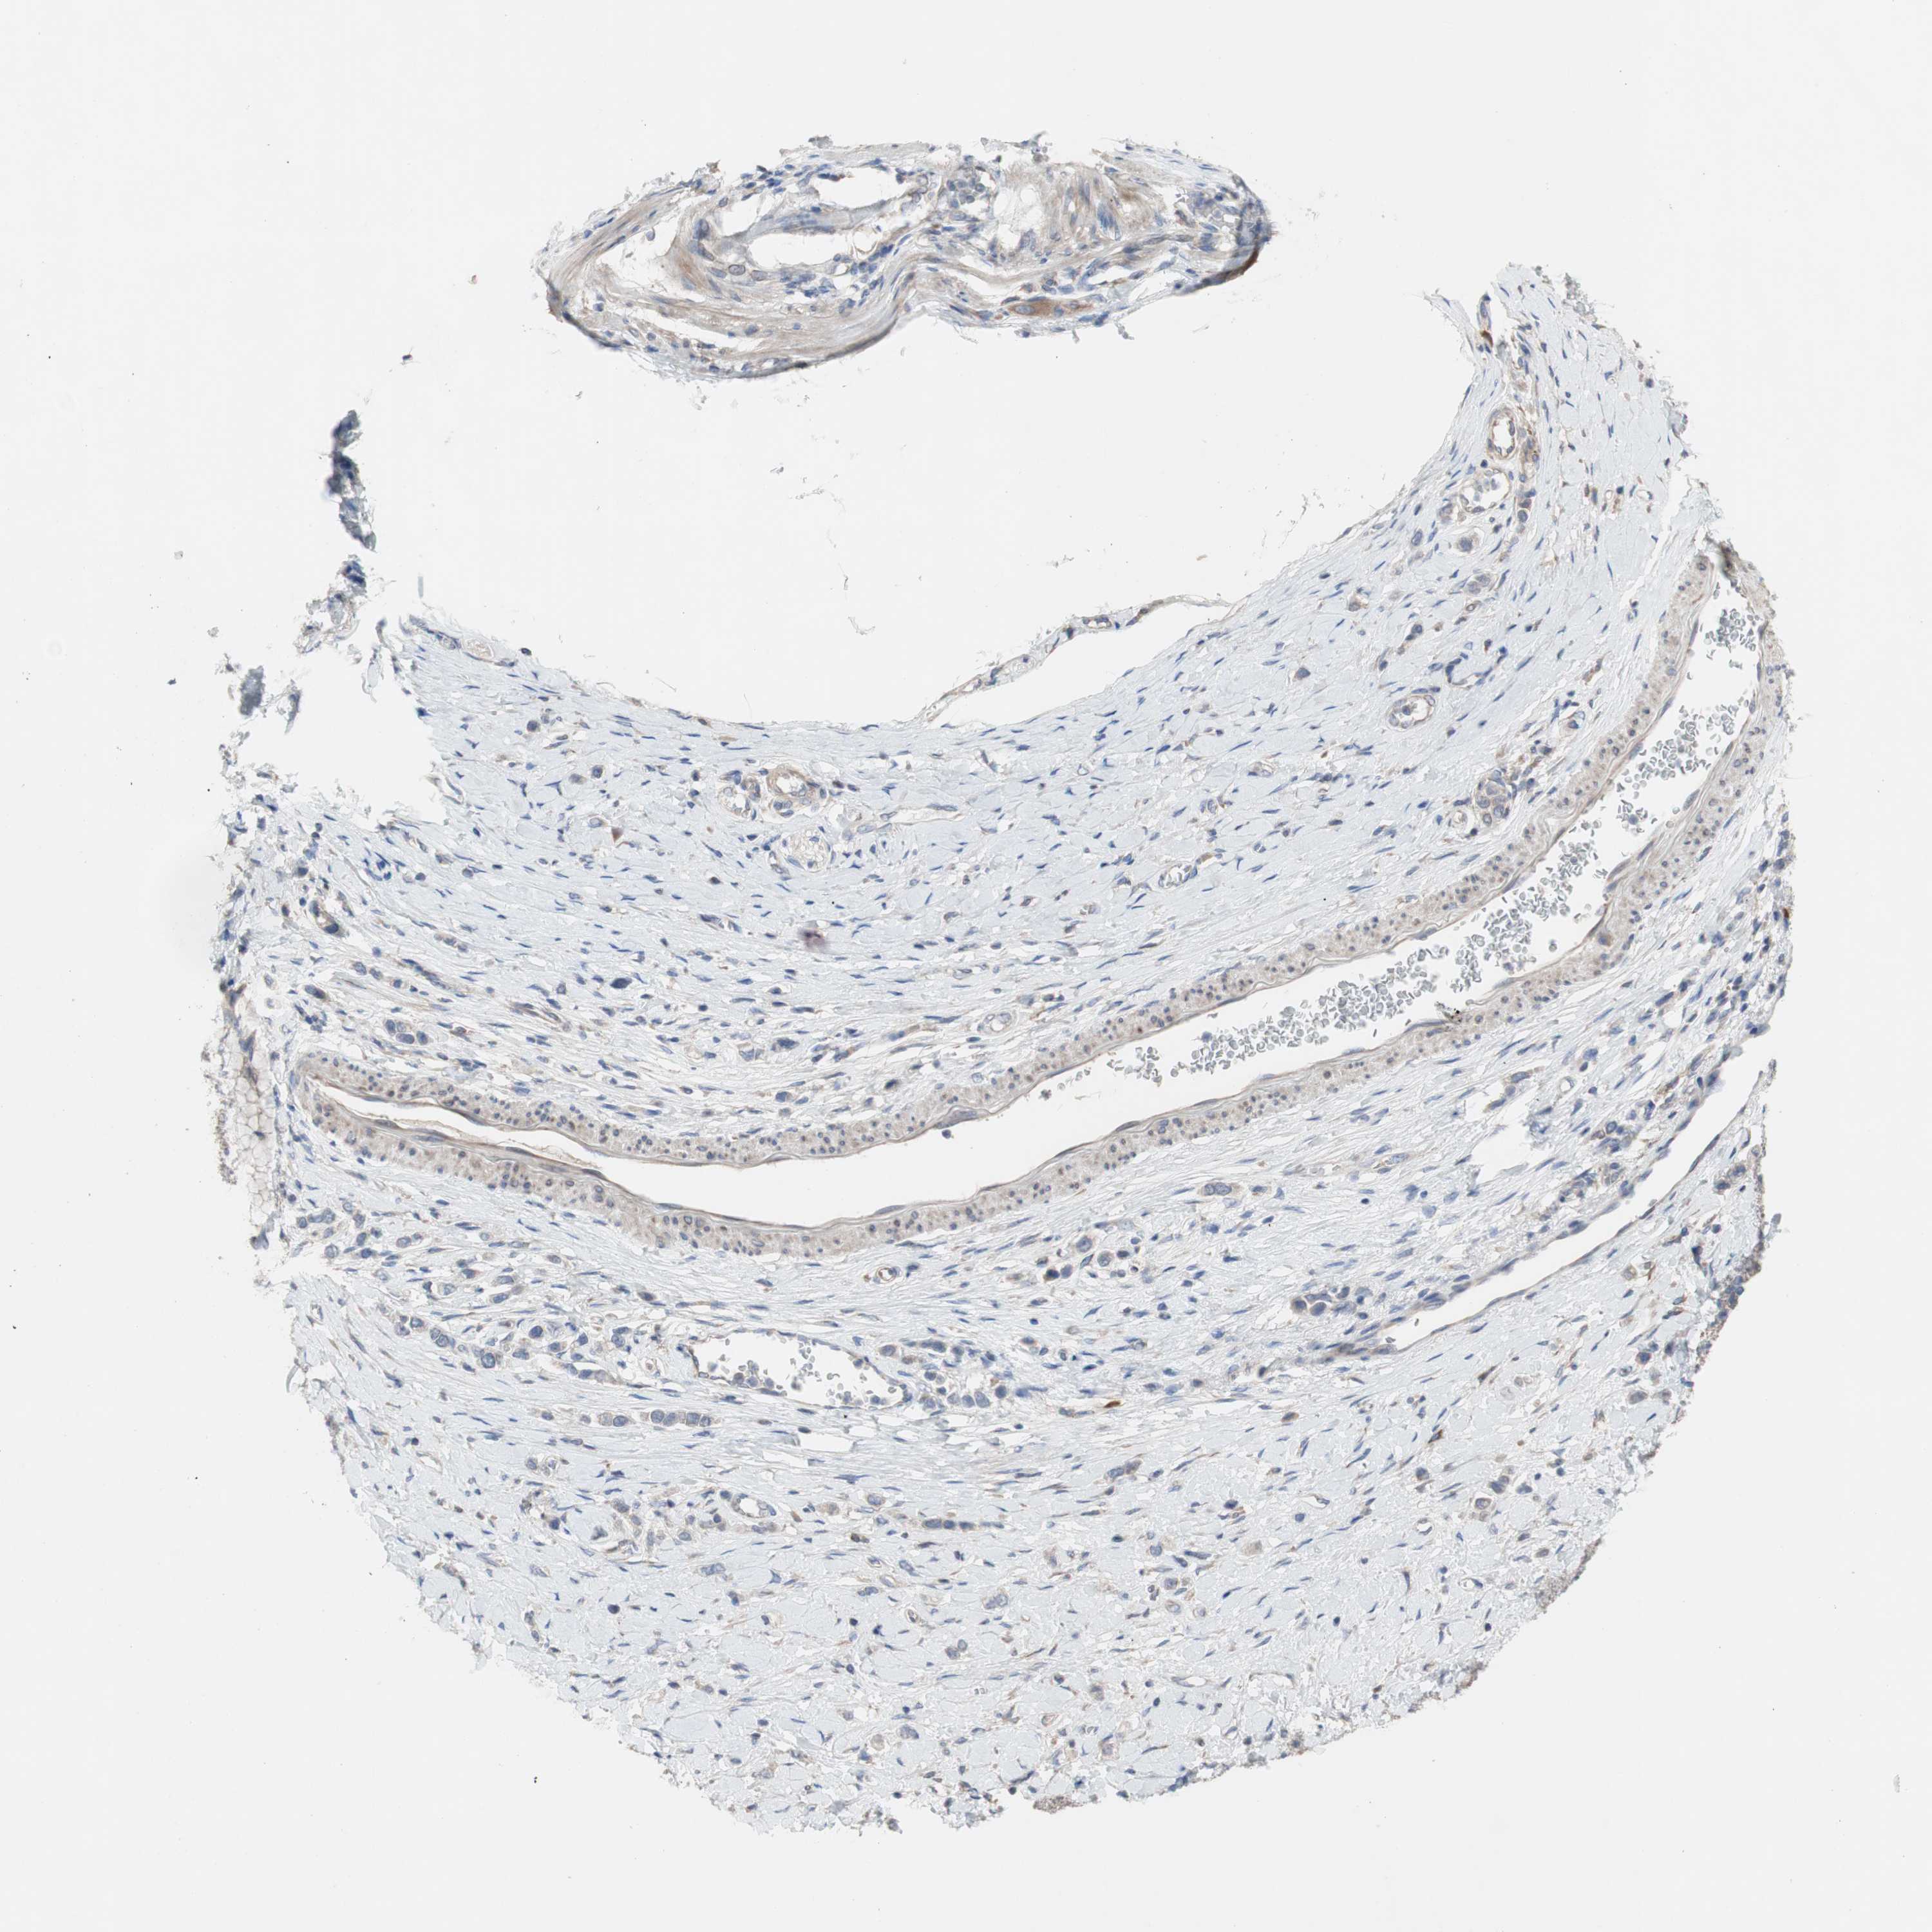

STOMACH CANCER - Protein expressioni

A mouse-over function shows sample information and annotation data. Click on an image to view it in a full screen mode. Samples can be filtered based on level of antibody staining by selecting one or several of the following categories: high, medium, low and not detected. The assay and annotation is described here.

Note that samples used for immunohistochemistry by the Human Protein Atlas do not correspond to samples in the TCGA dataset.

Antibody stainingi

Antibody staining in the annotated cell types in the current human tissue is reported as not detected, low, medium, or high, based on conventional immunohistochemistry profiling in selected tissues. This score is based on the combination of the staining intensity and fraction of stained cells.

Each image is clickable and will lead to virtual microscopy that enables deeper exploration of all samples and also displays staining intensity scores, fraction scores and subcellular localization as well as patient and tissue information for each sample.

Antibody HPA009295

Staining

High

Medium

Low

Not detected

Intensity

Strong

Moderate

Weak

Negative

Quantity

>75%

75%-25%

<25%

None

Location

Nuclear

Cytoplasmic/membranous

Cytoplasmic/membranous,nuclear

Adenocarcinoma, NOS